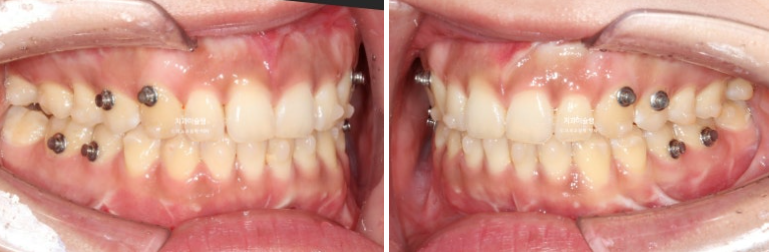

25년 6월 14개 장치를 모두 낀 후 모습입니다.

25.06

어금니 교합을 안정시키기 위한 고무줄 거는 고리가 여럿 붙어있습니다

수술 직후 변색이 되었던 아래 앞니는 신경이 돌아오며 정상 색깔을 회복중입니다.

교합은 좋은편이며

배열도 거의 완성이 되었습니다.